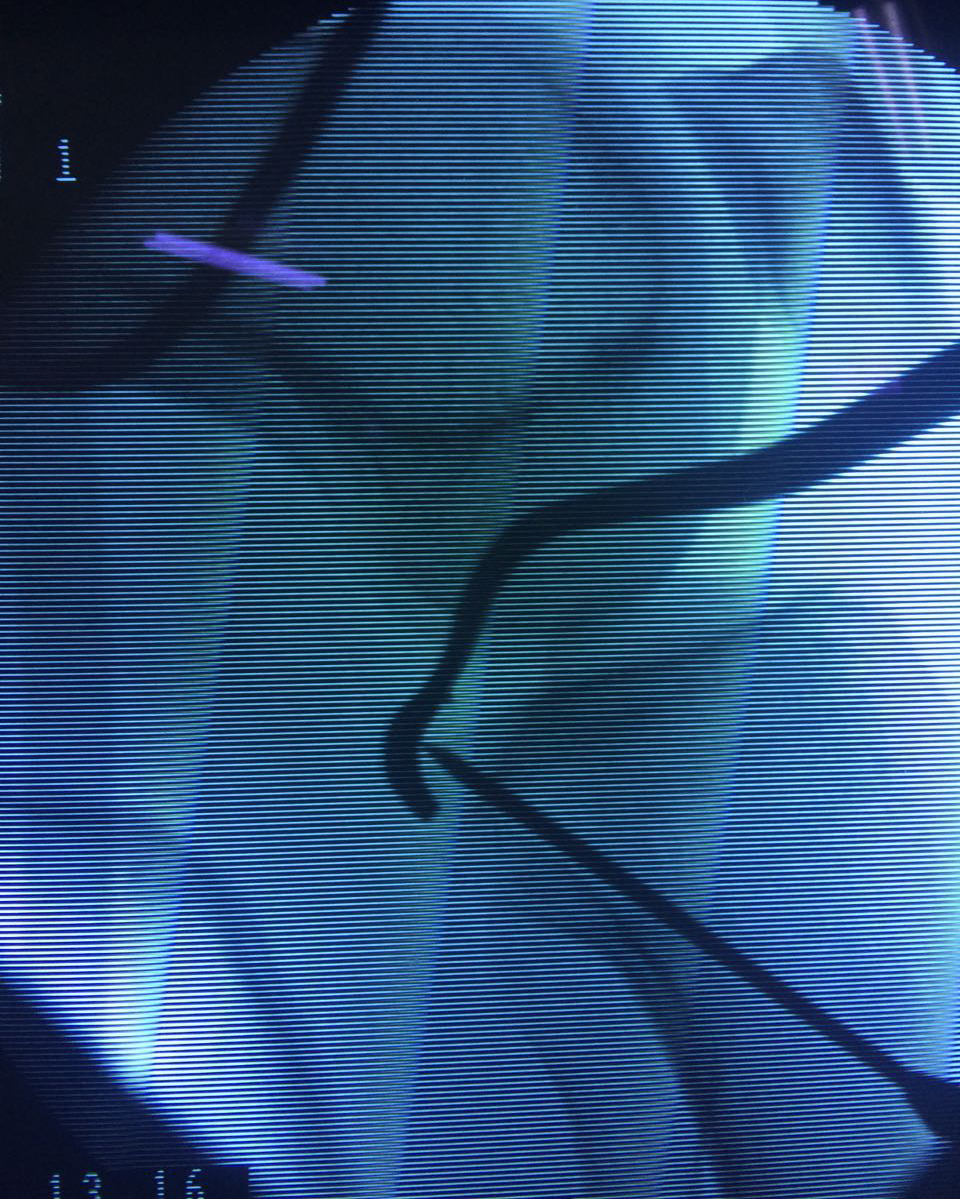

La artroscopia de rodilla es un cirugía en el cual la estructura interna de la articulación es examinada ya sea para realizar un diagnostico o para realizar un tratamiento, este procedimiento se realiza utilizando un instrumento parecido a un pequeño tubo llamado artroscopio.